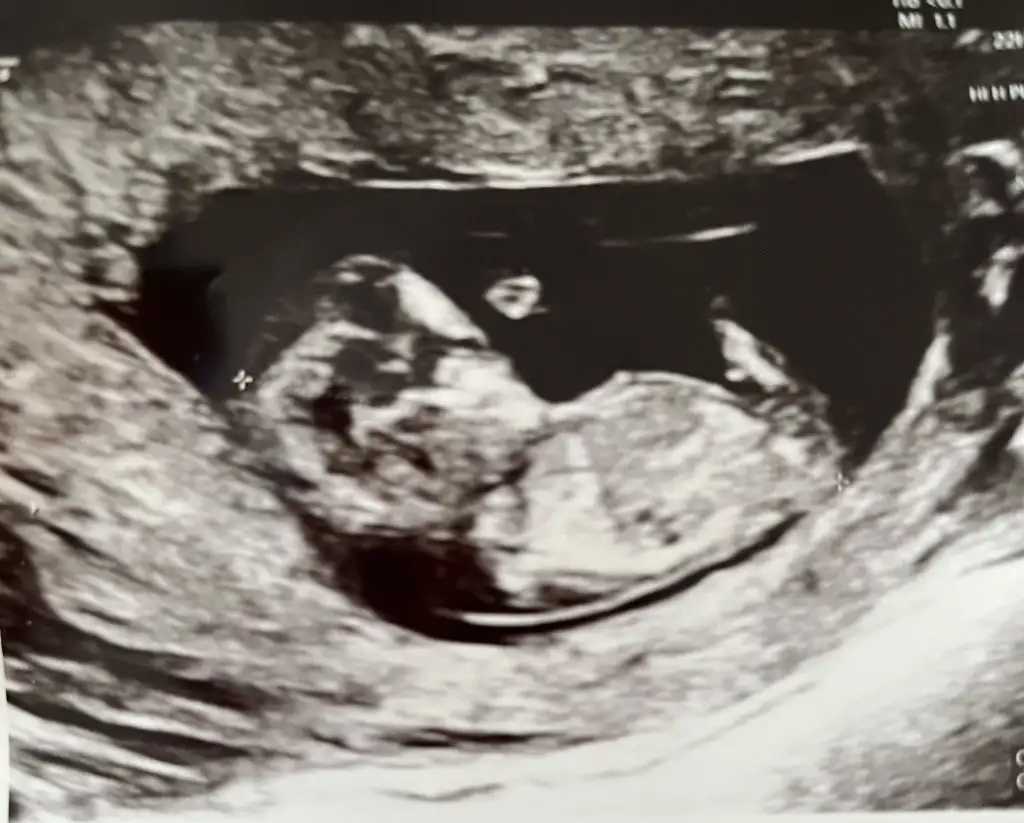

Muhtemelen duyulur ulstrasona göre benim 6+6da duyulmuştuKızlar 8 haftalık benim ama ultrasonda bir hafta geri çıkıyor yarın gidicem 7 haftalık olacak muhtemelen karından kalp atışı duyulur mu acaba

Erkek gibi hissettim doktor cinsiyet söyledimiMerhaba kızlaarr, tahmin de bulunabilir misiniz? 11+5 haftalıkEki Görüntüle 3544387

Minik kendini gösterdi ve kalp atışı gördük maşallahinsanın boş gebelik sonrasında bunu görüp şahit olması müthiş duygu maşallah rabbim sağlıkla ilerleyip kucaklarımıza almayı nasip etsin inşallah

Bence erkek öyle hissettim oğlumun fotoğrafına benziyorMerhaba kızlaarr, tahmin de bulunabilir misiniz? 11+5 haftalıkEki Görüntüle 3544387